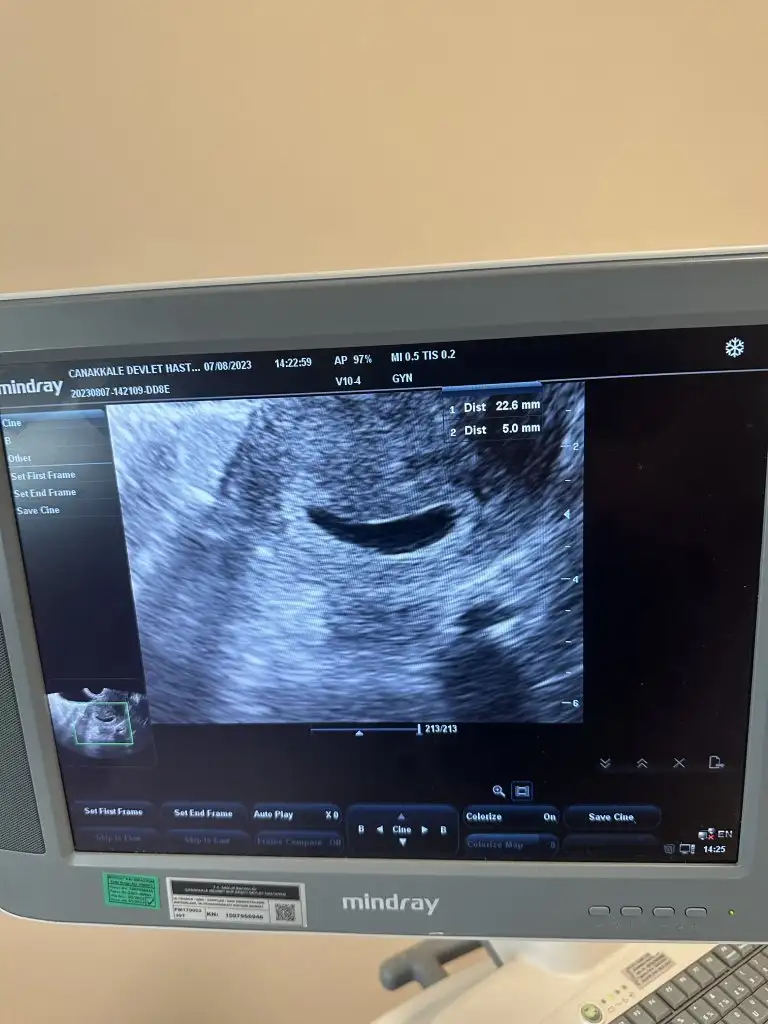

İnşallah bir sonraki randevu da her şey yoluna girer kese bu hafta da genelde yuvarlak ovalimsi oluyor ama şuan sağlıksız demek için erken bir sonraki randevuda belli olur net. Kese boyu kaç mm söylemiş miydi doktorunuz? Genel de kese 25 mm ve üzerindeyse içinde bebeğe ait bulgu yoksa o zaman bol gebelik sağlıksız gebelikten söz ediliyor benim ilk transferim öyle olmuştu ne yazık ki ama bu 6+3 de netleşmiştikızlar merhaba

17 Temmuz da transfer oldum. 7 Ağustosta keseyi görmek için doktora gittik ve şekli böyleydi

Doktorum çok olumsuz konuştu sağlıksız olabilir gibi şeyler söyledi.

Kese şeklim bozuk mu ? İnternette birsürü şey okudum düşük riski çok gibi. bilgisi olan var mı

Üstte 22 mm diye yazıyor zaten boyu.İnşallah bir sonraki randevu da her şey yoluna girer kese bu hafta da genelde yuvarlak ovalimsi oluyor ama şuan sağlıksız demek için erken bir sonraki randevuda belli olur net. Kese boyu kaç mm söylemiş miydi doktorunuz? Genel de kese 25 mm ve üzerindeyse içinde bebeğe ait bulgu yoksa o zaman bol gebelik sağlıksız gebelikten söz ediliyor benim ilk transferim öyle olmuştu ne yazık ki ama bu 6+3 de netleşmişti